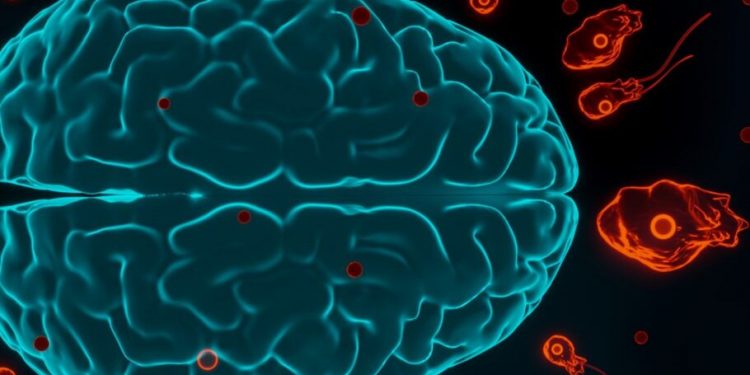

انقلابی در درمان بیماریهای مغز: استفاده از یک انگل عجیب

مغز ما توسط یک سد محافظتی محکم پوشیده شده که مانع ورود بسیاری از مواد مضر به آن میشود. این سد مانند یک نگهبان سختگیر است که اجازه ورود هر چیزی را به مغز نمیدهد. اما همین سد، مانع بزرگی برای درمان بسیاری از بیماریهای مغزی شده است.

دانشمندان برای حل این مشکل، به سراغ یک موجود بسیار کوچک و غیرمنتظره رفتهاند: یک انگل! این انگل که معمولاً در بدن گربهها زندگی میکند، توانایی خاصی دارد. او میتواند از سد محافظ مغز عبور کند!

دانشمندان با استفاده از روشهای پیشرفته علمی، این انگل را طوری تغییر دادند که بتواند دارویی خاص را به مغز برساند. این دارو میتواند به درمان بیماریهای مغزی مانند سندرم رت کمک کند. سندرم رت یک بیماری نادر است که باعث اختلال در رشد مغز میشود.

این انگل با وارد شدن به سلولهای مغز، میتواند دارو را درست به جایی که نیاز است برساند. این روش جدید میتواند انقلابی در درمان بیماریهای مغزی ایجاد کند و به بسیاری از بیماران کمک کند.